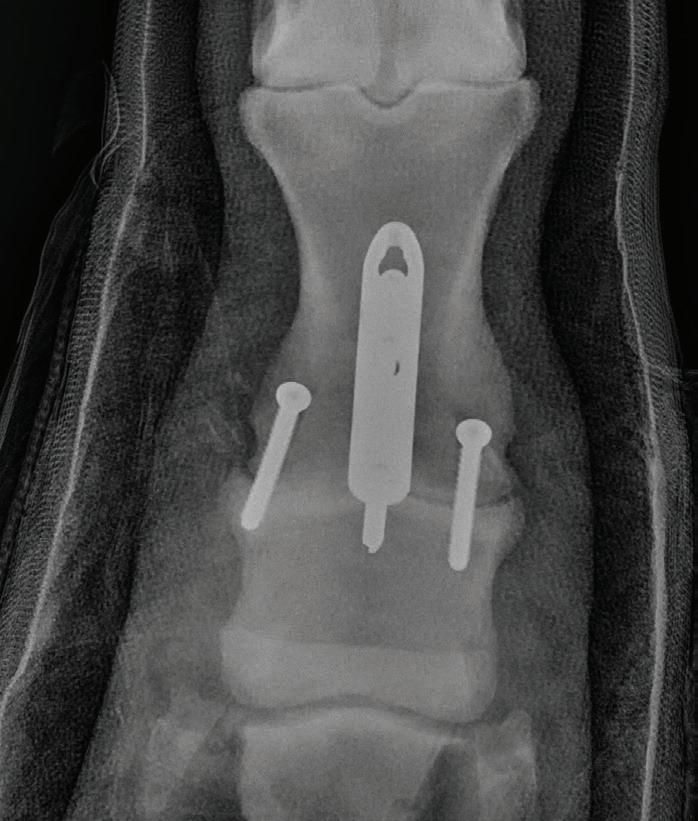

Case Report – Proximal interphalangeal (PIP) joint arthrodesis in a warmblood

32